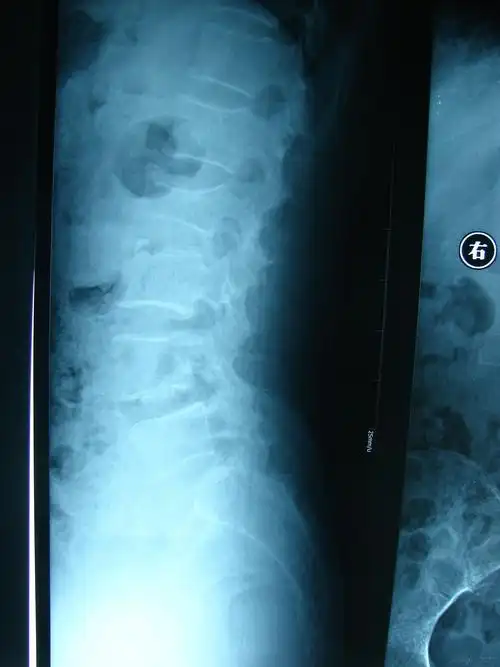

患者,女,55岁 第二腰椎爆裂性骨折